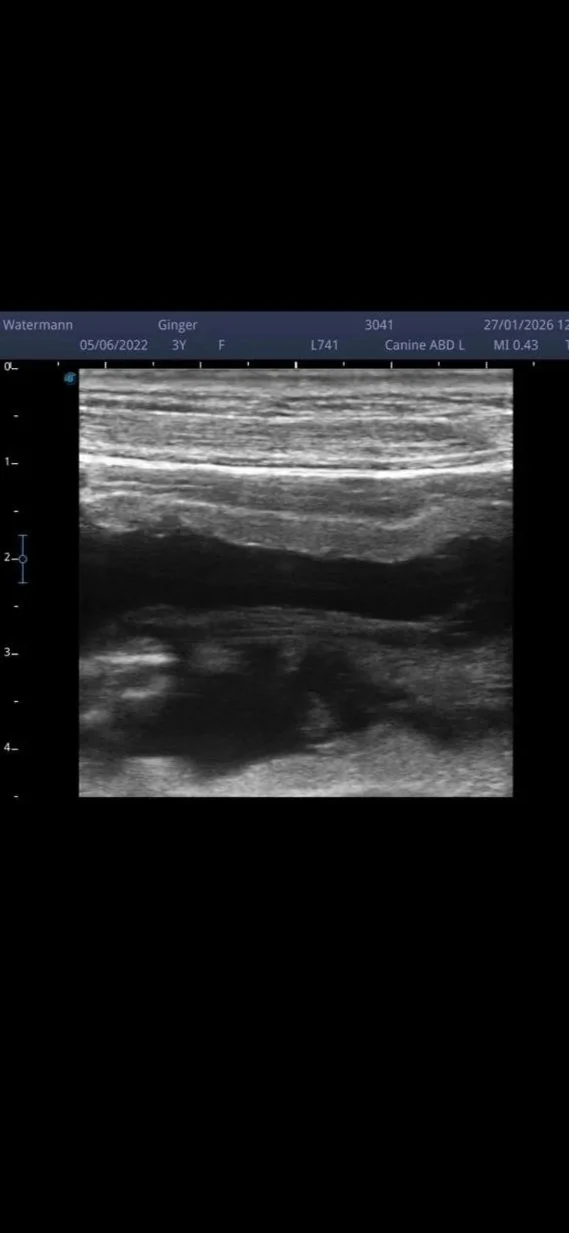

Beim Ultraschall konnten bereits zwei Welpen gesehen werden – es dürfen also mindestens zwei kleine Labradore erwartet werden.